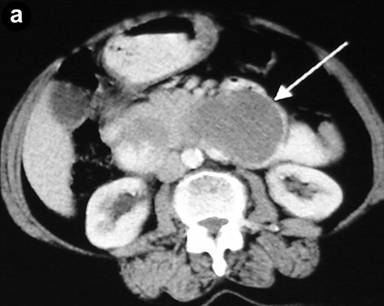

Abdominal ultrasonography showed a distended gallbladder without any calculi, prominent intrahepatic biliary radicals, a (10 mm) common bile duct dilated to the lower end with no calculi, prominent main pancreatic duct and a 2.8x1.9 cm hypoechoic mass near the distal end of the common bile duct. An abdominal computed tomography (CT) scan confirmed the dilatation of the common bile duct and the main pancreatic duct, and revealed an ill-defined hypodense mass 6.5x5.5 cm in size arising from the uncinate process of the pancreas (Figure 1). The mass involved the duodenum with an extension to the duodenojejunal flexure. The proximal duodenum was found to be dilated. The CT scan suggested the diagnosis of a pancreatic mass with duodenal infiltration. Upper gastrointestinal endoscopy was performed showing esophagitis and extraneous compression in the duodenal bulb. A side view endoscopy was performed and showed a long pedicle-like structure extending from the duodenal bulb into the distal duodenum along the medial wall of the second part of the duodenum (Figure 2). The distal end of this structure, the ampulla and the distal duodenal lumen could not be visualized. An attempt was made to pull the distal end of the structure using biopsy forceps but without success. Besides these findings, no ulcers, strictures or growths were found in the duodenum. In view of the endoscopic findings, the CT scan was again reviewed. The mass initially described as originating from the uncinate process was suspected to be intraluminal within the distal duodenum with a smooth outline at the distal end. However, this mass could not be defined as separate from the pancreas. In addition, a characteristic sign of “duodenal wall invagination” was observed in the dilated first part of the duodenum (Figure 3). Barium meal examination of the upper digestive tract showed a well defined smooth lobular filling defect in the dilated first part of the duodenum (Figure 4). Given the above findings, a duodenal polypoid mass of unknown nature was suspected. A side view endoscopy was repeated and endoscopic ultrasonography (EUS) was also performed. During this examination, a large polypoid mass with normal overlying mucosa was seen in the proximal duodenum (Figure 5a). The ampulla was seen as separate from the polyp and was found to be normal as was the visualized distal duodenum (Figure 5b). Endoscopic ultrasonography revealed a homogenous echogenic mass occupying the submucosa in the duodenal bulb with a normal pancreas which was not involved by the mass (Figure 5c). A biopsy taken from the polyp showed non-specific changes in the mucosa.

Figure 1. CT scan showing hypodense mass involving the distal duodenum and the uncinate process of the pancreas, and extending to the duodenojejunal flexure (arrow), causing dilatation of the proximal duodenum. |